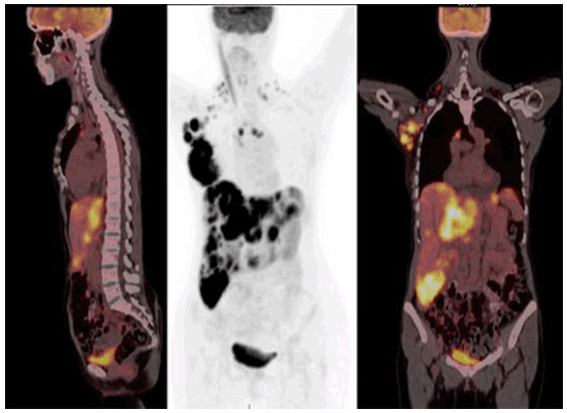

The examination revealed right axillary lymphadenopathy and an ulcerated scan breast tumor. The patient underwent a fine needle aspirate of the breast lesion that revealed an estrogen receptor positive adenocarcinoma. She also had a liver ultrasound which revealed multiple liver masses. A PET/CT scan (Figure 1) failed to reveal other organ or bone lesions, although lymphadenopathy was observed. She was managed with intravenous fluids, calcitonin intramuscularly thrice, furosemide daily and IV pamidronate during her first three days of inpatient treatment. She left the hospital at that point with calcium of 10.4 mg/dL, but declining anti-cancer treatment. The patient complied with the recommendation to drink at least 2 L of fluids daily.

Figure 1: Fused PET/CT scan of patient at time of initial presentation. FDG uptake is demonstrated in the breast, axilla, liver, internal mammary and supraclavicular lymph nodes. The middle image is a maximal intensity projection of FDG uptake by in the coronal plane. There is a notable lack of bone metastases in these images.